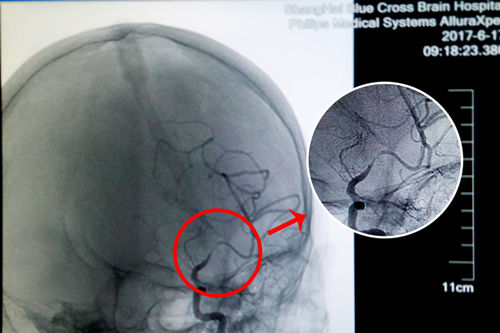

由于术前DSA检查得知盛阿姨的血管狭窄程度超过70%,球囊扩张支架置入手术存在较大的难度和风险,但这并没有难住李振并主任,他认为努力争取挽救患者生命的宝贵时机更为重要。经过一系列详细周全的术前准备,李主任和同事们开始了手术。

站在手术台前的李主任,表现出的是与平日不同的冷静和沉着。经术中精准测量发现,患者盛阿姨血管狭窄达到了77%,血管非常狭窄,使放置球囊扩张支架的难度更大。好在李主任积累了丰富的DSA手术经验,经过仔细小心的操作,导丝成功地通过了狭窄的血管。李主任用他的“血管艺术”使濒临枯萎的血管重新绽放出了生命的活力,最终原本非常狭窄的血管腔顺利张开了:“……将球囊扩张支架置入狭窄处,观察后准确释放球囊扩张支架,再造行3D造影,显示血管扩张,血流恢复正常。(摘自术后小结)”。

术前DSA影像显示,患者大脑中动脉血管70%以上狭窄